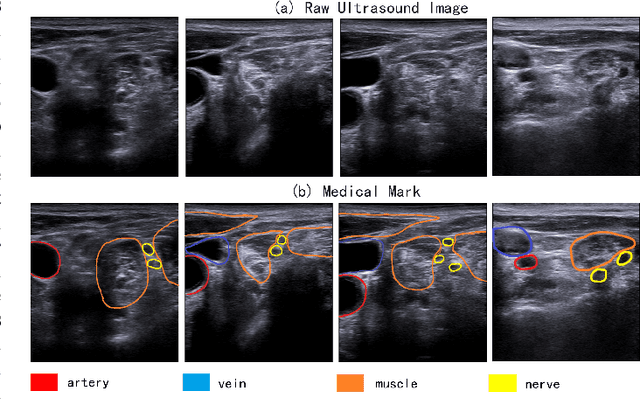

The identification of nerve is difficult as structures of nerves are challenging to image and to detect in ultrasound images. Nevertheless, the nerve identification in ultrasound images is a crucial step to improve performance of regional anesthesia. In this paper, a network called Brachial Plexus Multi-instance Segmentation Network (BPMSegNet) is proposed to identify different tissues (nerves, arteries, veins, muscles) in ultrasound images. The BPMSegNet has three novel modules. The first is the spatial local contrast feature, which computes contrast features at different scales. The second one is the self-attention gate, which reweighs the channels in feature maps by their importance. The third is the addition of a skip concatenation with transposed convolution within a feature pyramid network. The proposed BPMSegNet is evaluated by conducting experiments on our constructed Ultrasound Brachial Plexus Dataset (UBPD). Quantitative experimental results show the proposed network can segment multiple tissues from the ultrasound images with a good performance.